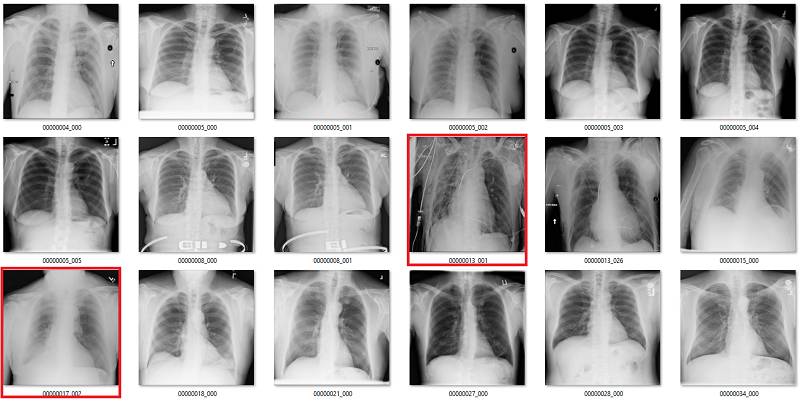

这部分要说该数据集中基于标签的图像。它们是随机选取包含 18 张图像的序列集,并非精挑细选。

我尽量保持谨慎,当一个案例模棱两可的时候,我选择标出标签类别。在所有图像中,红色 = 明显错误的标签;橙色 = 怀疑态度,我没有指出这个问题,但是不能排除这种怀疑。(出于临床诊断的习惯 :p)

心脏扩大(Cardiomegaly)

纤维化(Fibrosis)

真正类

绿色是真正类,其它的是错误的标签。

真负类

前 18 张有 1 到 2 个有争议,后面 18 张中红框都是错误的。

假正类

红色的都是错的,数据集中也出现了旋转和扭曲等异常情况(用红色问号标记)。

假负类

红色部分为严重错误标注。